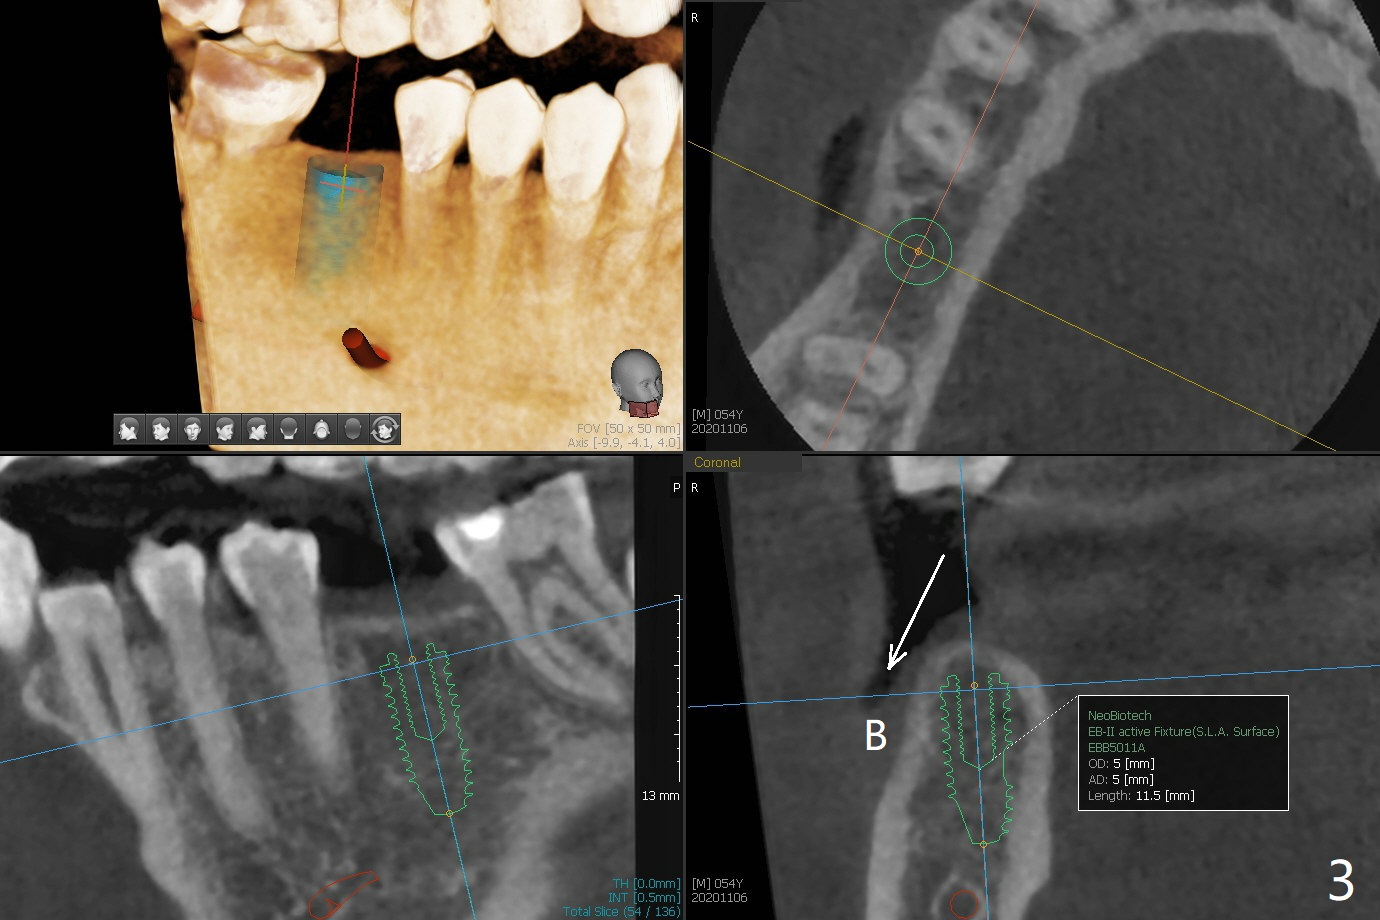

54岁男缺失右下6大约20-30年,但是右上6却没有过度萌出,因为右下7好像近中移位(图一:箭头)。3年前在没有CT检查下,根尖片设计表示植体直径可以4.5毫米(图二)。尽管现在CT检查表明骨头颊舌侧宽度允许5毫米植体(图三),4.5毫米植体(缺牙区近远中间隙小)可以让植体颊侧,舌侧骨板接近2毫米,加上导板应用,以及足够角化龈(临床检查显示),延长植体寿命是比较现实的事情。